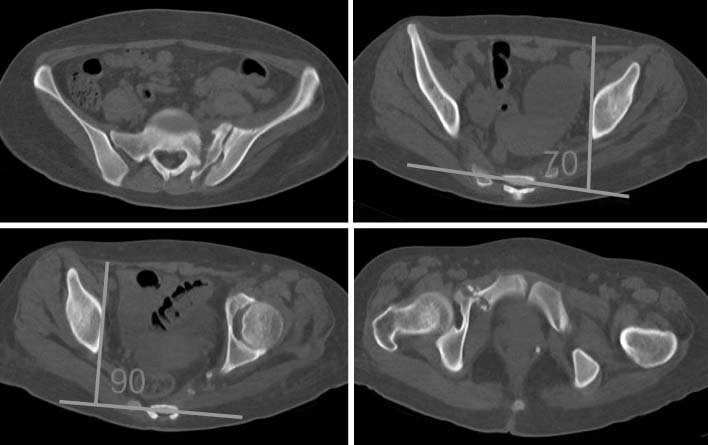

Two-dimensional computed tomography shows nonunion through the left sacrum and left pubic ramus and 20 degree internal rotation deformity.

Fig. 3 Two-dimensional computed tomography shows nonunion through the left sacrum and left pubic ramus and 20 degree internal rotation deformity.